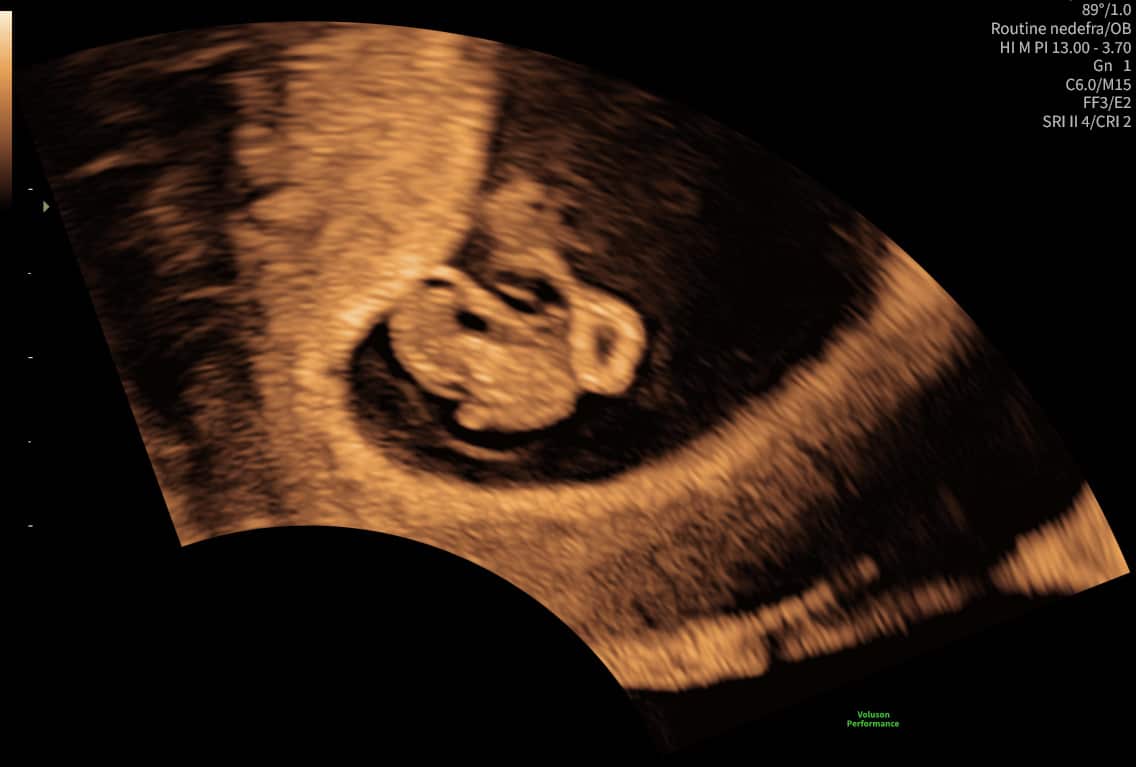

3D/4D-scanning

Oplev din baby i 3D/4D og få billeder med hjem.

Læs mere →